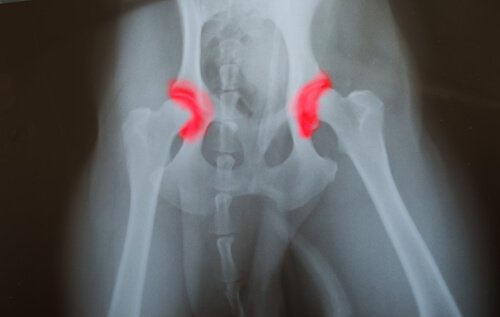

Worum handelt es sich bei Dysplasie?

Hüft- oder Ellenbogendysplasie ist eine vererbte Krankheit, die von Generation zu Generation weitergegeben wird. Die Knochen eines Gelenks, entweder der Hüfte oder des Ellenbogens, sind dabei nicht richtig platziert oder ausgerichtet.

So kommt es dazu, dass sie aneinander reiben und schädliche Bewegungen zur Folge haben. Das hingegen führt zu einer übermäßigen Abnutzung und fehlerhaften Funktion des Gelenks. Das Problem hierbei ist, dass die Krankheit still voranschreitet.